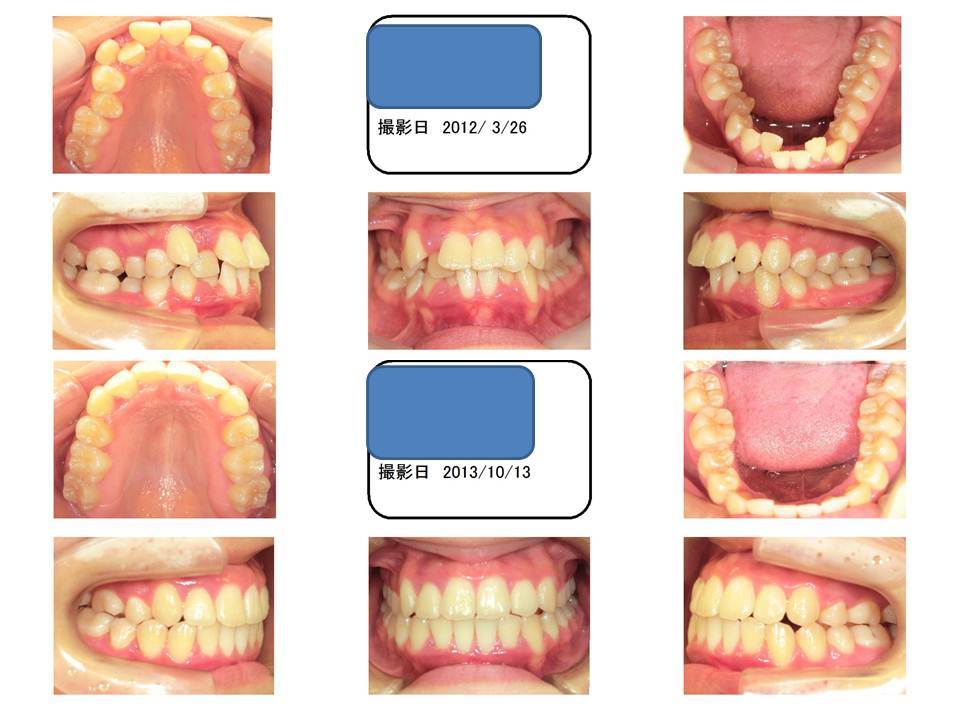

16歳 女性 凸凹 前歯部叢生

この症例は、八重歯です。八重歯は歯の並ぶだけの隙間が足りていないために起こります。

八重歯の症例を改善するには、隙間を確保しなくてはいけなくて、そのためには歯の本数を減らす必要があります。

通常は、上下左右の歯1本ずつ抜くのですが、このケースは上顎の左右2本を抜いています。なぜかというと、奥歯の咬み合わせが出っ歯だからです。

このケースで下の歯も抜いてしまうと、出っ歯になってしまうので、上の歯だけ抜いての治療となっております。

上左右一本ずつ歯を抜いて隙間を作り、前歯のデコボコ・八重歯を改善します。

ブラケット装置で矯正します。